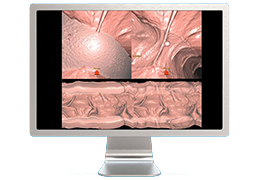

Performs 3D reconstruction and volume rendering.

Multi-planar slicing.

Oblique slicing.